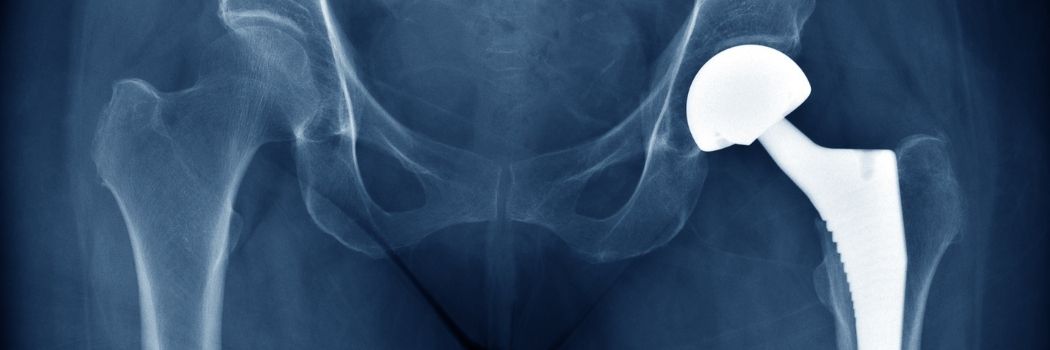

An x-ray of a hip replacement

We’re working on a new sugar-containing polymer that could one day help repair artificial joint implants like hip replacements.